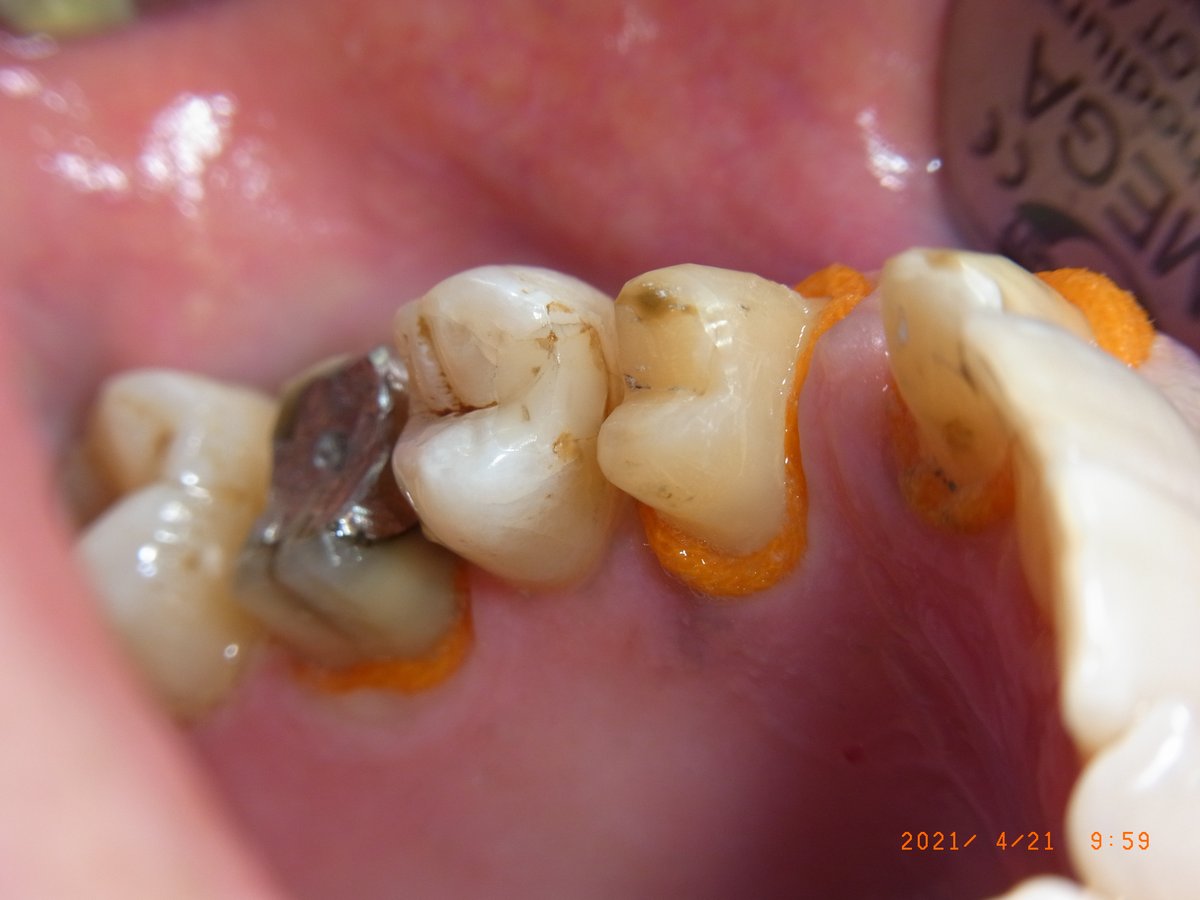

Gute Patienten- (durch Prophylaxe) und Sulcusvorbereitung (intragingivale, adrenalinhaltige Anästhesie, Faden Knit-Pak Gr. 2 (Fa. Premier) mit Racestyptine (Fa. Septodont), ca. 10 min Einwirkzeit) und möglichst knochentrockene Situation direkt vor der Abformung bleiben wichtig. (Anmerkung 7/2023: Die Abdruckspritze ist wieder dabei, weil sie die Luftblasen im Sulcus reduziert.)

Retraktionsfaden Knit-Pak Gr. 2 mit Racestyptine an den Frontzähnen des Oberkiefers: Der orange Faden öffnet den Sulcus für die anschließende Abformung.

Nahaufnahme: Der Faden liegt tief im Sulcus und verdrängt die Gingiva zuverlässig. Die knochentrockene Situation ist für eine fehlerfreie Sulcusabformung entscheidend.

Retraktionsfaden auch im Seitenzahnbereich. Die Abdruckspritze steht bereit, um unmittelbar nach Fadenentnahme mit der Zweitabformung zu beginnen.